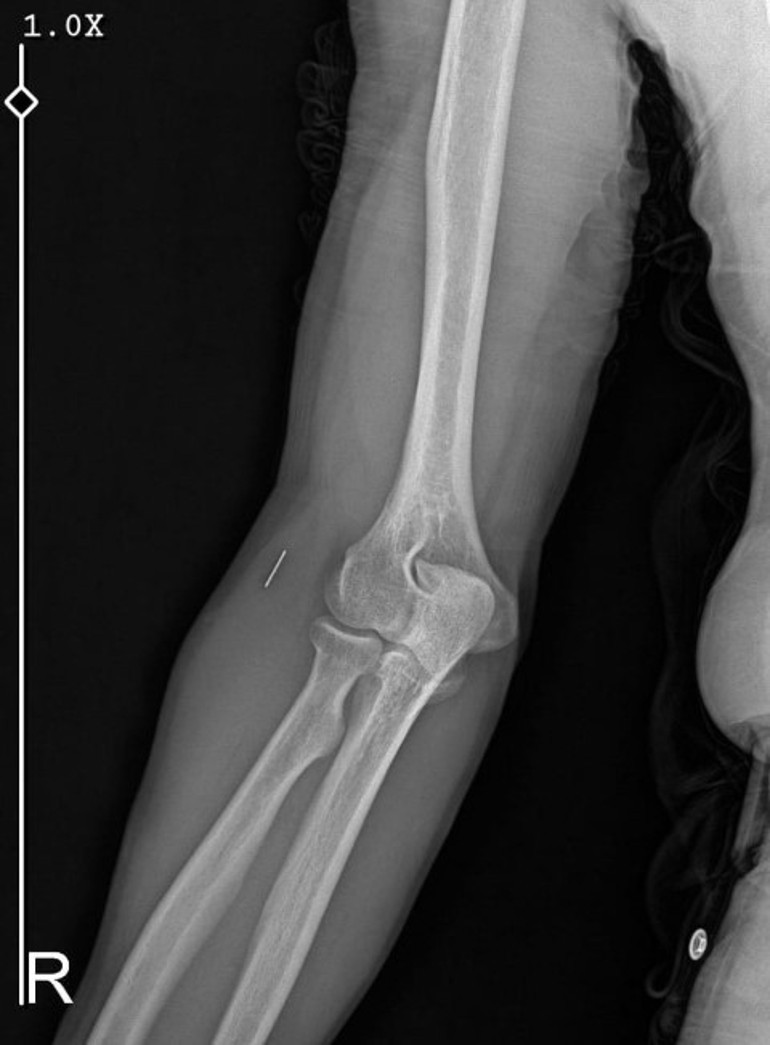

Ameliyatların ardından Güleryüz’ün kolunda bir metal parça bulunduğu ve bu parçanın parmak bölgesinden dirseğe doğru ilerlediği öne sürüldü. Ayrıca, fabrikada temizlik personeli olarak çalışan Güleryüz’ün, hastane sürecinde işten çıkarıldığı bilgisi edinildi.

İkinci hastanedeki ameliyatların ardından kolunda ağrılar hissettiğini dile getiren Güleryüz, “Doktorlara sürekli bileğime doğru ağrılarım olduğunu ifade etmeme rağmen beni dinlemediler. Sonradan kolumda metal kaldığını öğrendik. Bunun bir ihmal olduğunu düşünüyoruz. Ben 9 aydır çalışamıyorum. Kalp rahatsızlığım nedeniyle yüzde 46 engelliyken şu anda yüzde 75 engelli durumuna düştüm. Erken emeklilik dilekçesi verdim ancak henüz sonuç gelmedi. Bu konuda mağdurum.